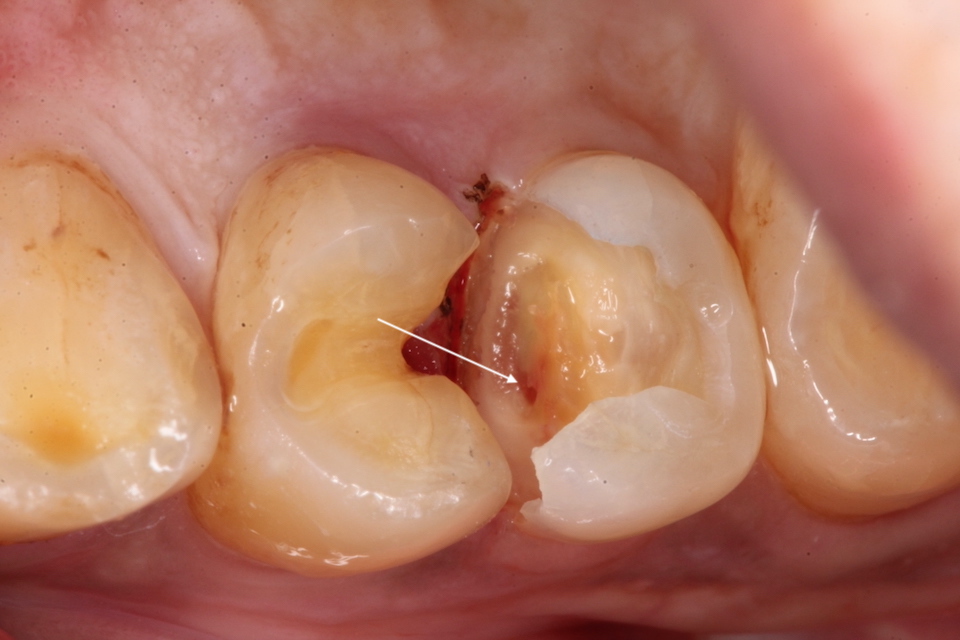

下顎7番の頬側歯茎部カリエスの原因 2025.06.04